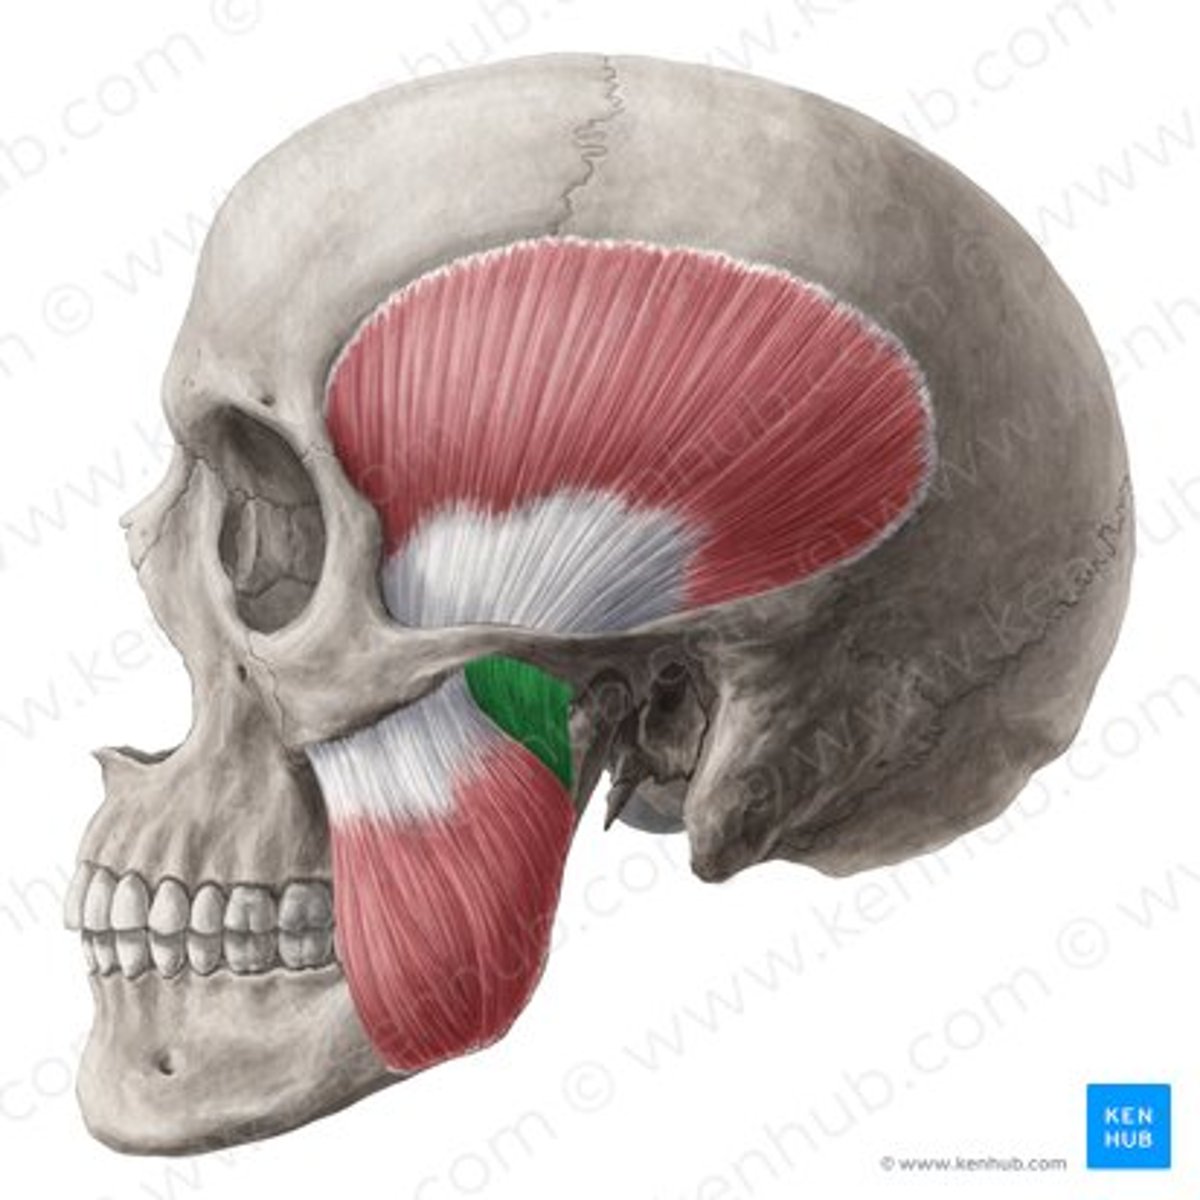

deep masseter

superficial masseter

temporalis

lateral pterygoid

lateral pterygoid, superior part

lateral pterygoid, inferior part